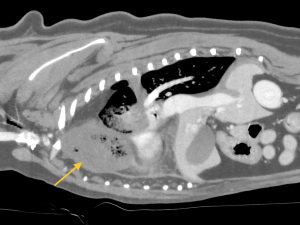

持参されたCTを拝見したところ、右前葉の腫大、内部に細かい泡、血行不良、胸水貯留が認められ、右前葉の肺葉捻転と診断しました。

黄色矢印=捻転した肺